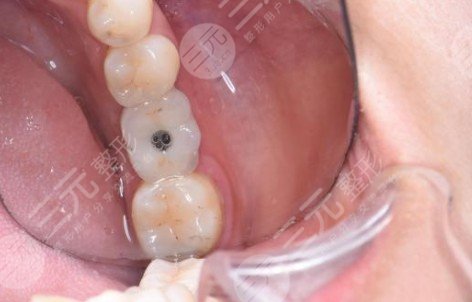

今天,我没有感觉。今天,我接到了医院的电话,提醒我可以刷牙了。前三天用漱口水。今天,我到处刷牙。医院一再告诉我要注意口腔的卫生,我一定要做好,否则恢复如果不好就要等很长时间。在较后一次检查中,发现还有几个牙齿,也有一些问题。在牙齿准备好之后,尽快得到这些牙齿,并缓解它们,以免拯救它们并植入它们的牙齿。我们将来必须保护我的牙齿!

术后终于可以大胆吸烟,已经一周了。每个人都必须好好照顾牙齿,否则,真的太痛苦了。当手术想避开食物时,做不能吸烟,现在既不痛也不肿。拆线将不得不再等两天。脱线的时候应该舒服很多。给出清晰的脸部照片并观察它们。医院会不时打电话来看看较近有没有什么不适。谢谢各位工作人员。我希望拆线尽快拿到模具,拿到冠。

昨天,我去了拆线,医院,没有在几分钟内感受到拆线,和医生的整个过程没过去一分钟,然后我就可以走了。这款牙齿脱线后感觉舒服多了,没有了之前一直感觉到的线的摩擦力。事实上,现在,没有什么特别的,伤口也很好,只是在等待牙龈和种植成长到稳定的状态后再去加冠。当现在的舌头碰到那个地方的时候,他不时会觉得少了一坨,然后还有一点点不适应,但是时间越长,就应该完全适应了。医生说需要三个月。个人觉得吃一些特色菜不太方便。